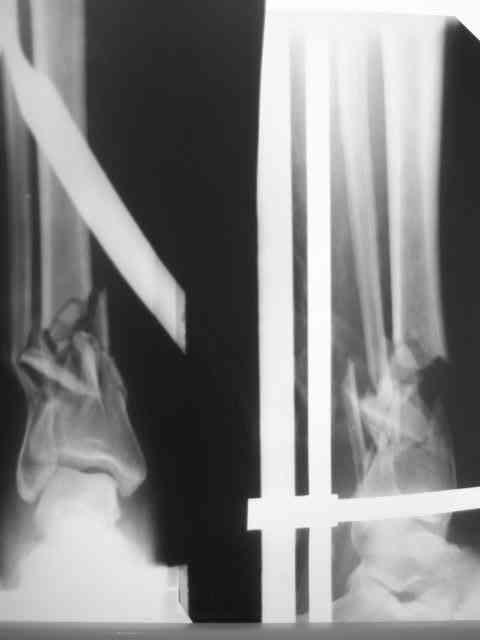

Перелом н/3

Из истории выяснилось: травма 29.01.07 Диагноз: Открытый оскольчатый перелом н/3 костей голени (якобы 2 Б Каплан), при поступлении операция из трех букв и скелетное вытяжение + остальная терапия. Затем выполнили остеосинтез штифтом (походу Эксперт стоит) видимо хотели зацепится за дистальный отломок, но скорей всего все было нестабильно и накинули этот сокращенный АВФ. На сегодня (162 дня): Больная ходит с ограниченной нагрузкой на конечность (трость). Движения в г/стопе качательные. Трофика мягких тканей не настораживает. Воспаления м/тканей нет. В планах: 1. удаление штифта 2.Наложение стандартного АВФ с фиксацией стопы и устранение всех смещений 3.Резекция нежизнеспособных костных отломков 4.Остеотомия в/3 большеберцовой кости с последующей дистракцией и замещением дефекта. Хотелось бы выслушать мнение по этому случаю! Возможен ли вариант если на опер.столе удастся устранить смещения одномоментной репозицией АВФ и не удалять штифт а производить транспорт большеберцовой кости на штифте? И стоит ли при таком коротком дистальном отломке пытаться блокировать в низу (имеется в виду в АВФ) Спасибо.